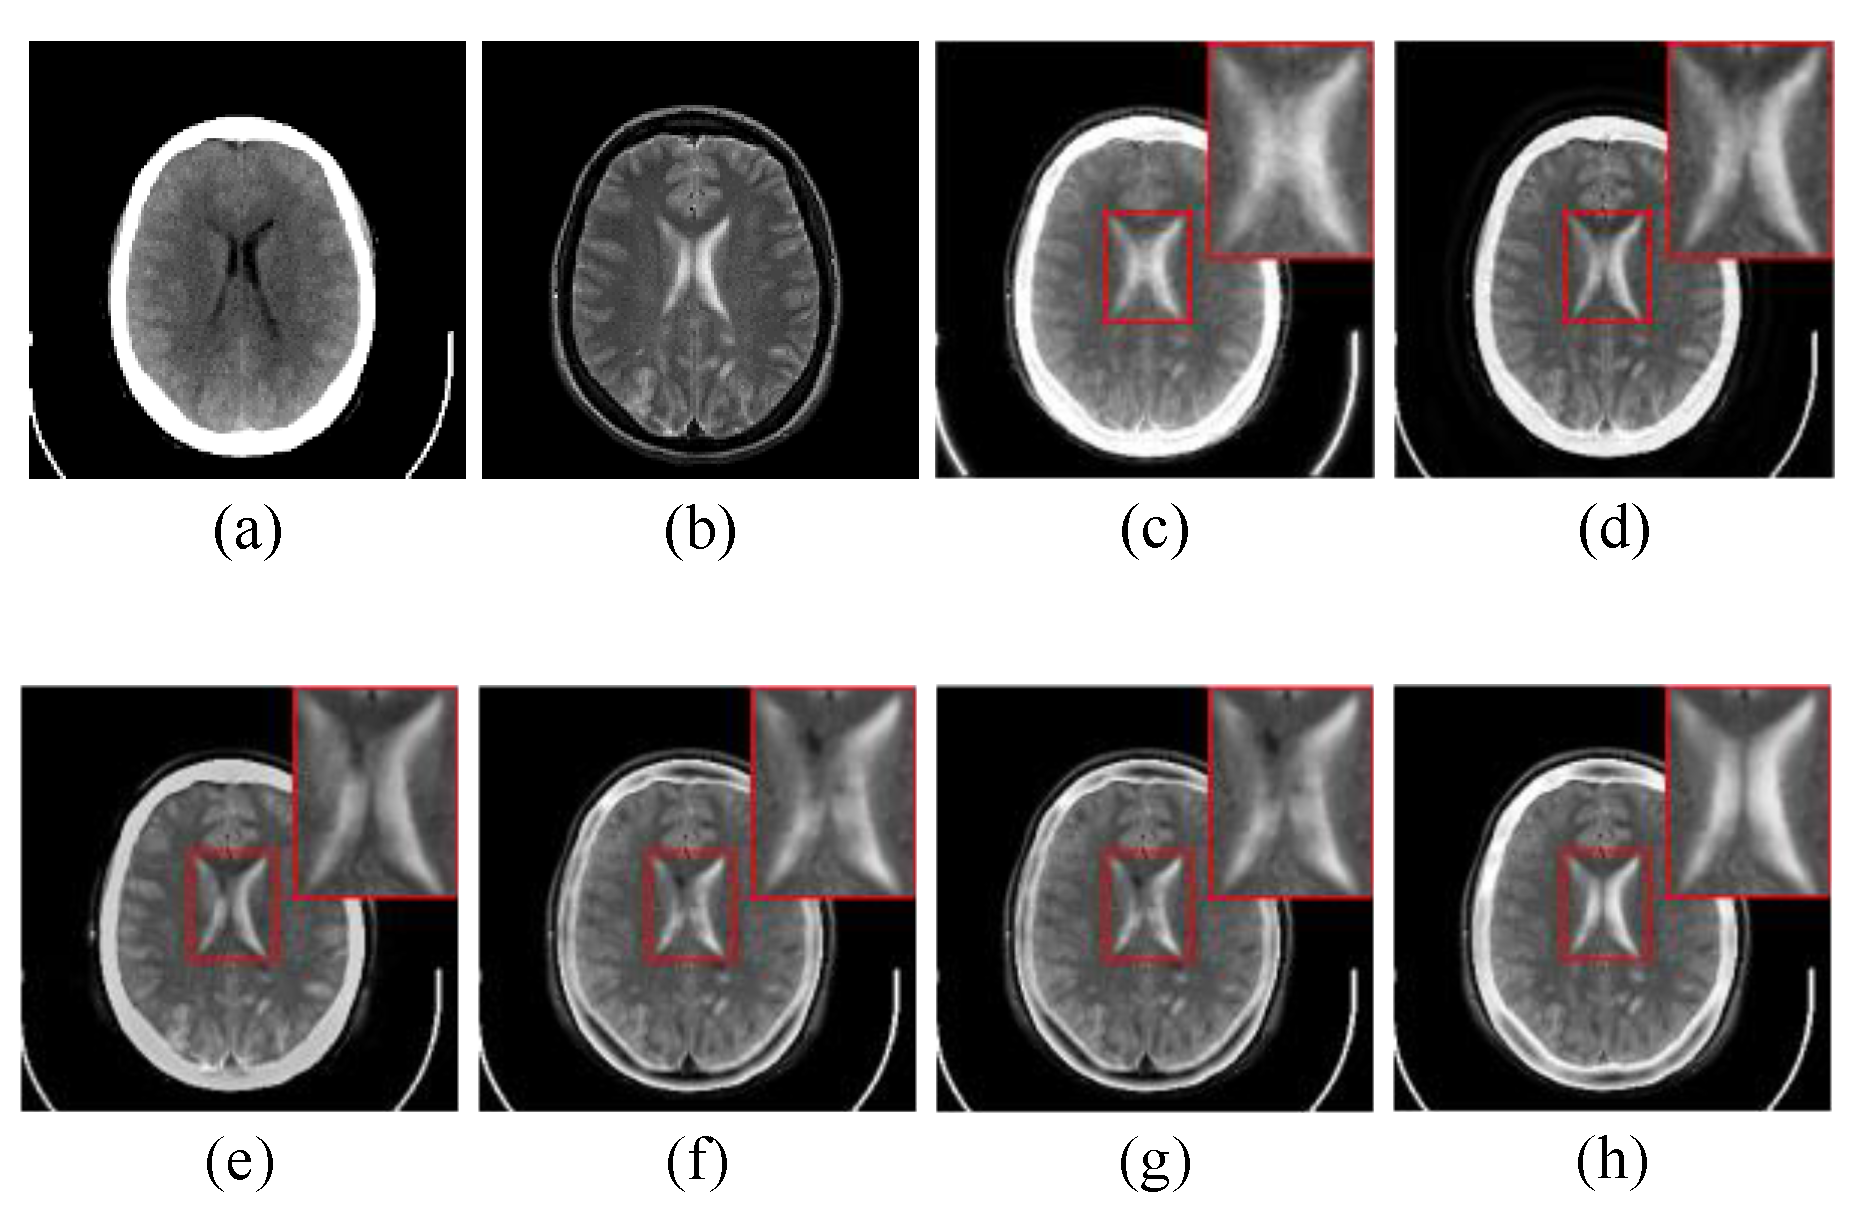

4.2.1. Subjective Visual Evaluation